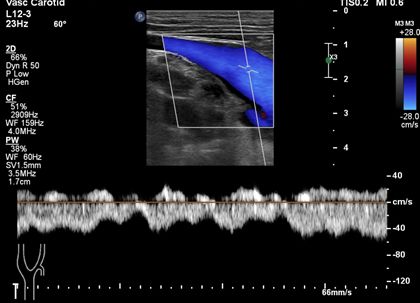

患者双侧颈内静脉张力较高,探头加压时管腔不易压瘪。

双侧颈内静脉失去受心脏搏动影响的搏动性频谱特征。双侧颈内静脉表现为连续带状血流频谱,流速降低,频谱形态略受颈总动脉搏动的影响。

双侧锁骨下静脉、颈外静脉和头臂静脉都为类似的连续低速带状血流频谱。

看一看正常的颈内静脉搏动性频谱形态: